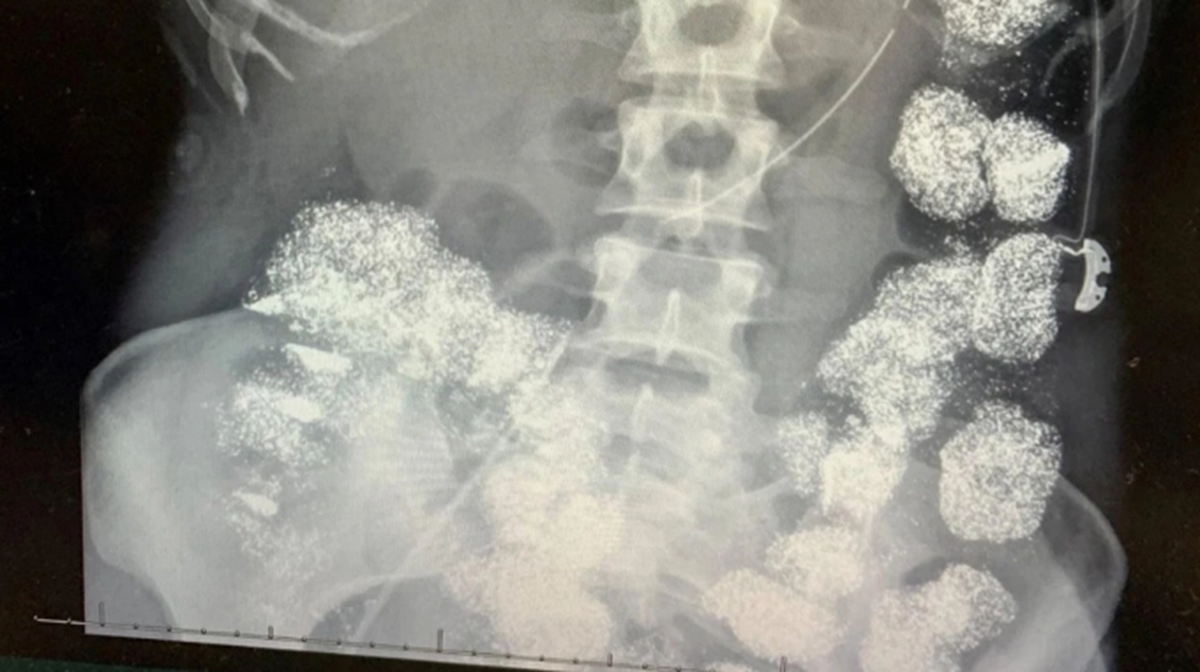

Tại viện sau khi thăm khám và làm các xét nghiệm kết quả xét nghiệm cho thấy nồng độ chì trong máu Pettey vượt mức 80 mcg/dL, gấp 8 lần ngưỡng an toàn. Phim chụp X-quang ghi nhận kim loại nặng lấp đầy đại tràng và dạ dày, thậm chí xâm nhập vào xương. Các bác sĩ nhận định bệnh nhân không thể vô tình nuốt lượng chì lớn như vậy nên lập tức báo cảnh sát điều tra người thân.

Cơ thể Hannah Pettey bị lấp đầy bởi chì. Ảnh: Hartselle Police Department.